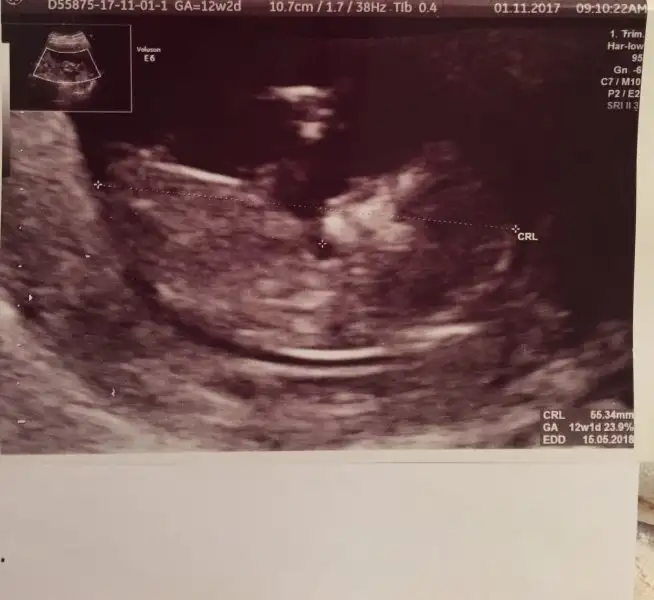

Canim bana erkek.gibi geldiFotograf atmayı başarabildiysem nub’a göre bana da bişeyler söyleyebilir misinizz?

Ay maşallah erkek gibi mi bu bebiş acaba.Fotograf atmayı başarabildiysem nub’a göre bana da bişeyler söyleyebilir misinizz?

Canim bana erkek.gibi geldi

Ay maşallah erkek gibi mi bu bebiş acaba.

Yaa ultrason fotogrAfi var mi cok merak ettimmSağol canım evet ben de gördüm valla. Gözümle görmesem inanmazdım aklına gelebilecek herşey erkek diyordu

Buyur canım tahminleri alayımYaa ultrason fotogrAfi var mi cok merak ettimm

Ayy ben hic anlamam ki :)) ama bu forumda dolastim dolasali su ultrason fotograflarindan bir sey anladim. Kese genisse yukari dogruysa kiz, yanlamasina uzunsa erkek cikiyorBuyur canım tahminleri alayım

Onu ben de okumuştum fasülye gibiyse erkek nohut gibiyse kızAyy ben hic anlamam ki :)) ama bu forumda dolastim dolasali su ultrason fotograflarindan bir sey anladim. Kese genisse yukari dogruysa kiz, yanlamasina uzunsa erkek cikiyor